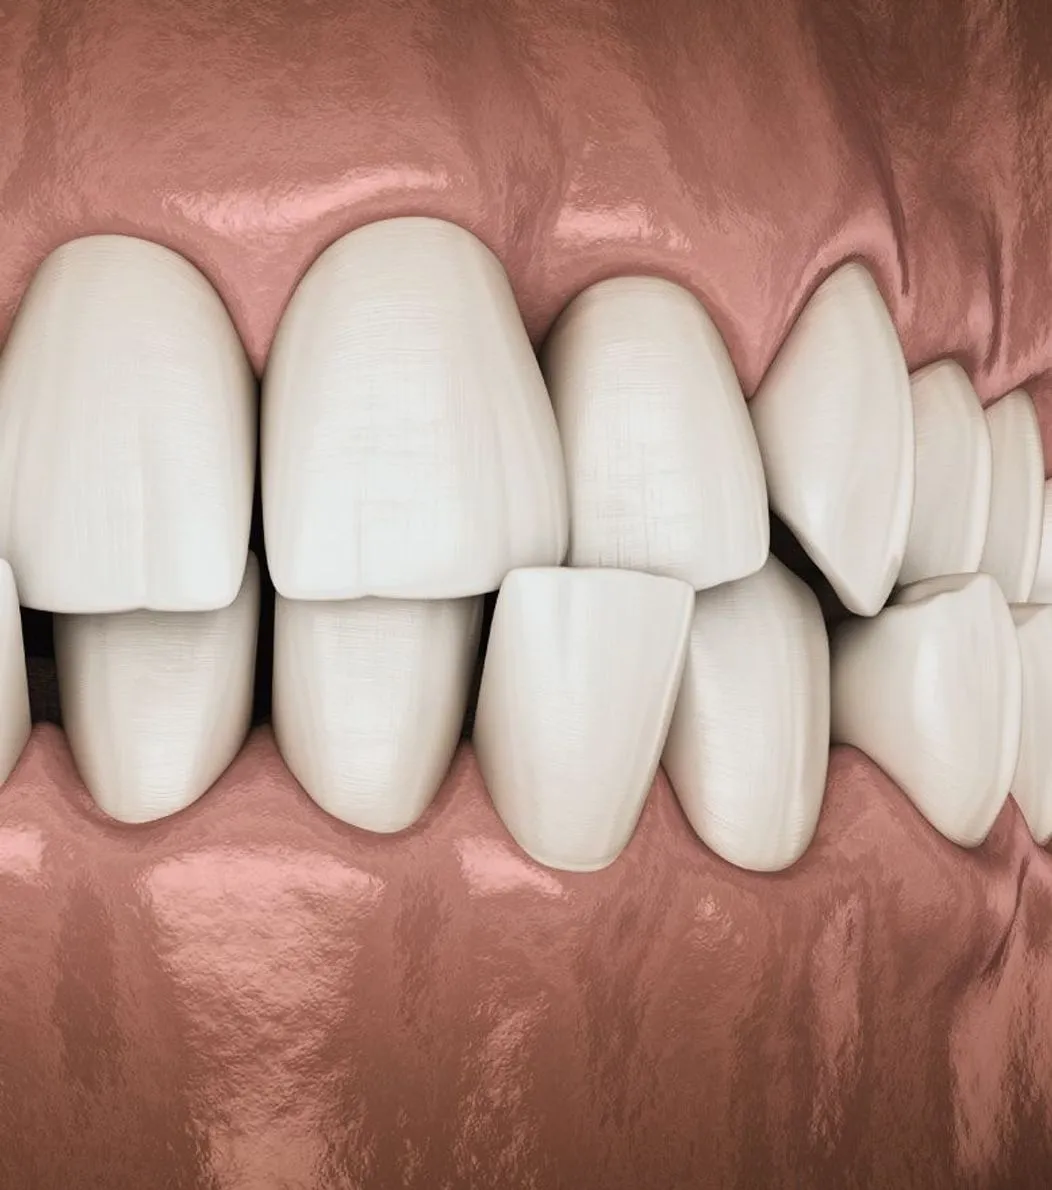

Dental implants are a long-term solution that feels and functions like a natural tooth. The implant is placed in the jawbone where it bonds with the bone, creating a secure foundation for a custom crown. Implants help maintain bone strength, improve chewing ability, and restore the appearance of your smile. With the right care, they can last for many years.